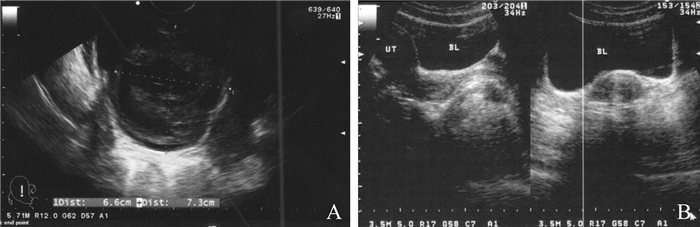

病例3 患者,39岁。因经阴道穿刺取卵术后2 h头晕,恶心,排少量肉眼血尿,伴下腹胀痛感于2018年1月23日在我院就诊。患者于2005年行人工流产1次,婚后未避孕5年未孕,2016年在我院行输卵管造影示左侧输卵管阻塞,右侧输卵管伞端积水,2017年2月行腹腔镜手术切除双侧输卵管,后因继发性不孕症在2017年共行3个周期IVF,分别获卵4、3、4枚,形成胚胎2、1、2枚,3次胚胎移植均未孕。2018年1月23日于我院行第4周期微刺激方案IVF,取卵日B超监测见左侧卵巢位于膀胱上方,术后穿刺针经过部分膀胱组织,获卵3枚。术后阴道穿刺点少量活动性出血,予纱块压迫数分钟后观察无明显活动性出血。嘱患者于观察室休息、多饮水,并注意排尿情况。术后2 h患者起身后诉一过性晕眩,恶心,排少量肉眼血尿,伴下腹胀痛感。观察患者情绪紧张,面色苍白,立刻予开放静脉通道,并予静脉输注葡萄糖氯化钠,低流量吸氧,体格检查:体温37.2 ℃,脉搏105次/分,血压132/93 mm Hg,呼吸25次/分。血常规:血红蛋白112 g/L,红细胞3.9×1012/L,白细胞12.0×109/L,中性粒细胞0.78,血小板203×109/L,红细胞比积0.402。经腹B超提示膀胱充盈欠佳,内可见不均质混合回声包块,大小约66 mm×73 mm(图 2A),考虑为膀胱损伤后膀胱出血。告知患者相关病情后,收治患者入院治疗,进行积极的心理支持,予静脉止血和预防感染,并口服镇静药物,留置22F三腔气囊导尿管。B超监测下使用50 ml注射器和预先加温至37 ℃的生理盐水进行手动膀胱冲洗。抽吸液为鲜红色,可见较多渣状血凝块。B超观察膀胱内混合回声团明显缩小(图 2B),可见雪花状散在小血块,抽吸液渐呈清亮粉色含少量渣状小血块。予生理盐水行持续膀胱灌洗至导尿管内尿色清,复查B超未见明显血凝块。复查血常规示:血红蛋白97 g/L,红细胞4.1×1012/L,白细胞10.5×109/L,中性粒细胞0.75,红细胞比积0.373,血小板199×109/L。凝血酶原时间12.5 s,纤维蛋白原3.15 g/L,活化部分凝血活酶时间29.5 s,凝血酶时间16.3 s。嘱患者多饮水,留置尿管3日后拔除尿管,并予口服止血、预防感染治疗3 d。拔除尿管后患者可自解小便,尿色清,无血尿、排尿困难。住院3 d后复查B超,未见膀胱内明显异常,出院。该周期形成胚胎2枚,因“珍贵胚胎”而取消新鲜周期移植,冻存胚胎。2018年4月20日行自然周期冷冻胚胎移植,移植2枚胚胎,未孕。

图 2 经阴道穿刺取卵术后并发膀胱损伤患者(病例3)的B超检查结果 A:治疗前可见膀胱有不均质混合回声包块;B:治疗后混合回声团明显缩小 |